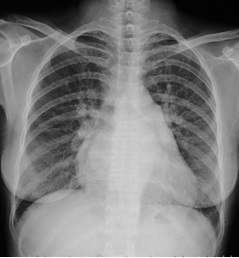

试题:根据下图请做出正确诊断

A.正常心脏

B.心肌病(普大心)

C.风湿性心脏病(梨型心)

D.主动脉型心(靴型心)